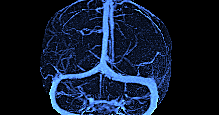

3D 동정맥영상

3D 동맥영상

3D 정맥영상

4D 혈관영상